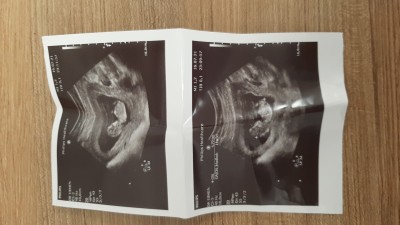

NUB TEORISINDEN ANLAYANLAR Cinsiyet hakkinda

kızlar anlayan varmı lütfen bakin

Gebelik haftası

13+0

Cinsiyet tahminlerini sol üst köşeden konu dışı sohbetten sorabilirsiniz

#nub